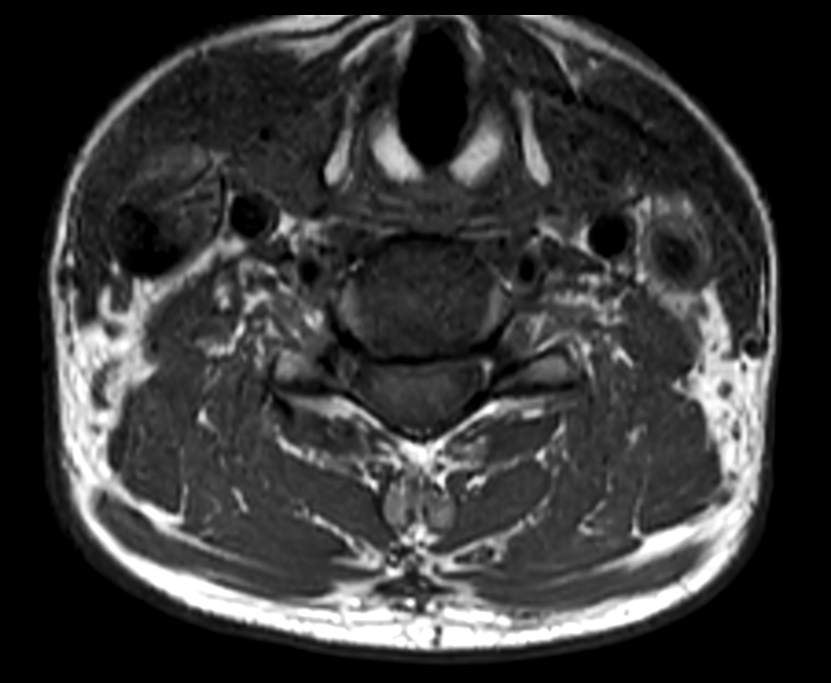

Axial T1w TSE

Axial T2w TSE

Axial mFFE